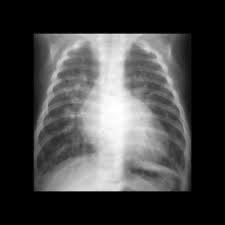

CXR: 심장의 Egg on side 소견